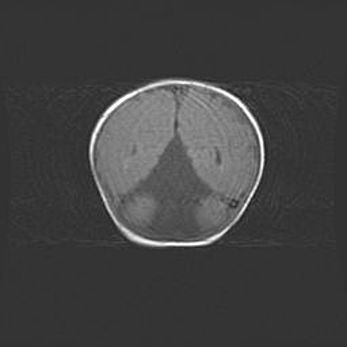

Церебральная ишемия II.

Возраст: 5 дней

Вес: 3400 г

Пол: женский

Окружность головы: 35 см

Срок гестации: 39 недель

Церебральная ишемия – это заболевание, характеризующееся недостаточностью (гипоксией) либо полным прекращением (аноксией) снабжения мозга кислородом по причине закупорки одного или нескольких сосудов. Это приводит к  что метаболическим расстройствам различной степени тяжести в тканях головного мозга, развитию коагуляционных некрозов и гибели нейронов.